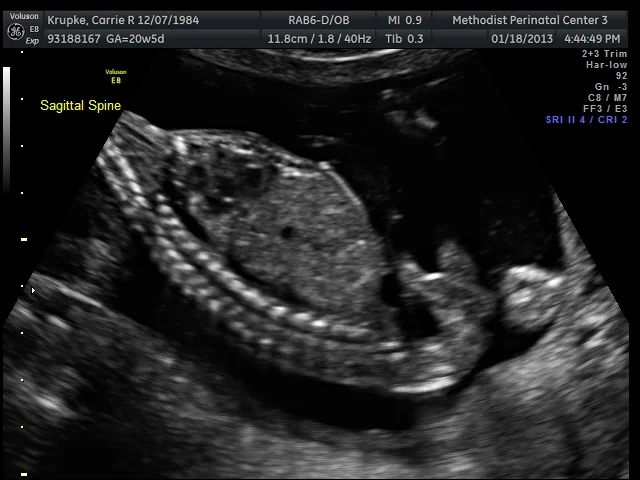

At several points in that 75 minutes, I’d look at the tech and try to read her face. She was so focused, she’d look concerned, especially when she was looking at the spine. I asked her a few times if everything was ok and she’d smile and say, “Yup, this is my focus face. This Peanut is moving around so much, I have to be quick to click for the photo. Spine looks fantastic!” I’ll admit, this kinda looks like an underwater sea-creature.